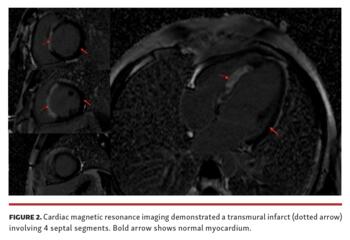

A 30-year-old patient who frequently uses cocaine presented to the emergency department with a 3-hour history of central chest pain and anterior ST-segment elevation on electrocardiogram. Emergent coronary angiography showed flush occlusion of the septal perforator (Figure 1A and Video 1) with retrograde filling from the right coronary artery (Figure 1B and Video 2). We opted for medical management as the pain was subsiding and the apparent infarct territory was small based on angiographic appearance. However, peak troponin T was subsequently elevated at 7538 ng/L. Cardiac magnetic resonance imaging demonstrated a transmural infarct involving 4 septal segments (Figure 2) resulting in moderate left ventricular systolic impairment (ejection fraction, 38%). The patient was discharged on dual-antiplatelet therapy, atorvastatin, ramipril, and bisoprolol. At follow-up, he was asymptomatic and his left ventricular ejection fraction improved to 50%.

Septal branches arising from the left anterior descending coronary artery supply the anterior interventricular septum in unison. In this unusual presentation of cocaine heart disease, occlusion of a single dominant septal perforator caused a large septal myocardial infarction, resulting in significant left ventricular impairment.